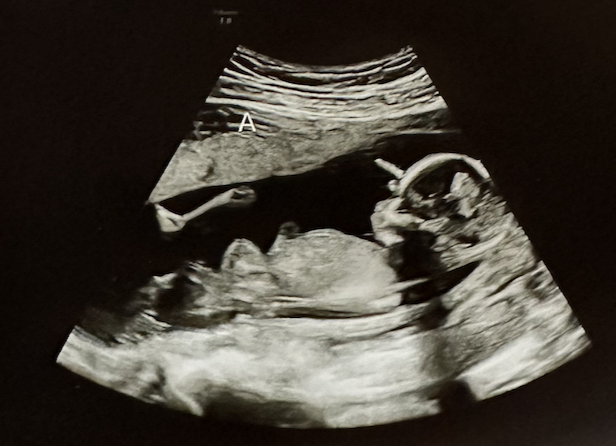

쌍둥이 임신기록 18주부터 21주까지 기록 (동산병원 배진곤교수님 초진, 현풍 행복한병원 정밀초음파)

우리 봄이와 가을이가 내 뱃속에서 무럭무럭 자라서 어느덧 27주차가 되었다. 단태아들은 30주가 넘어서도 ...